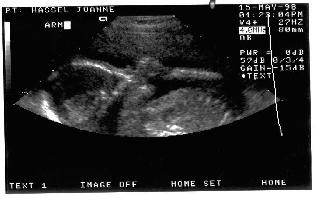

15 May 1998 - Sonogram of "Baby" Hassel

We sure were excited !